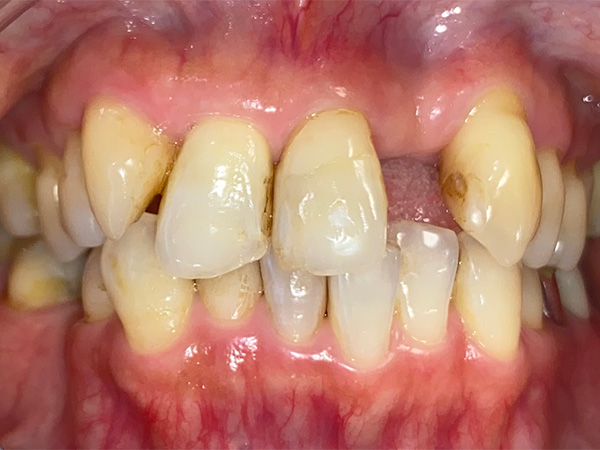

インプラント症例その1

術前

① 年齢層(一般的傾向) 60代

② 性別 女性

③ 主な主訴(受診理由の例)

• 歯を失ったため噛みにくい

• 自分の歯と同じように噛みたい

• 入れ歯が合わない

• 入れ歯が嫌、入れたくない

• 見た目が気になる

• 入れ歯、ブリッジ以外の方法を検討したい

• 事故で前歯が無くなったので、見た目を回復したい